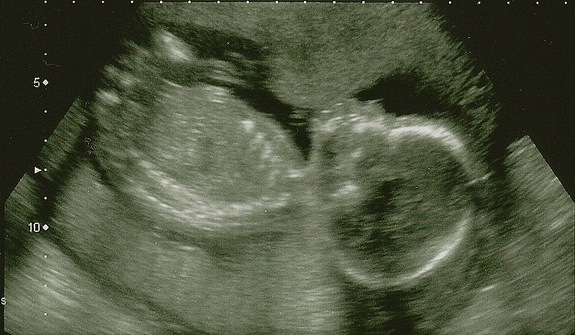

A mulher, que estava com pouco mais de cinco meses de gestação, teve um aborto espontâneo na última quarta-feira (26) e foi atendida na maternidade. A criança nasceu com 455 gramas e morreu logo depois, devido à prematuridade extrema.